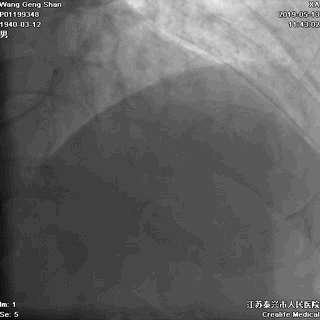

03 第一第二对角支保护

对角支导丝到位

左冠共计5根导丝

前降支近段支架植入后用非顺应性球囊高压扩张